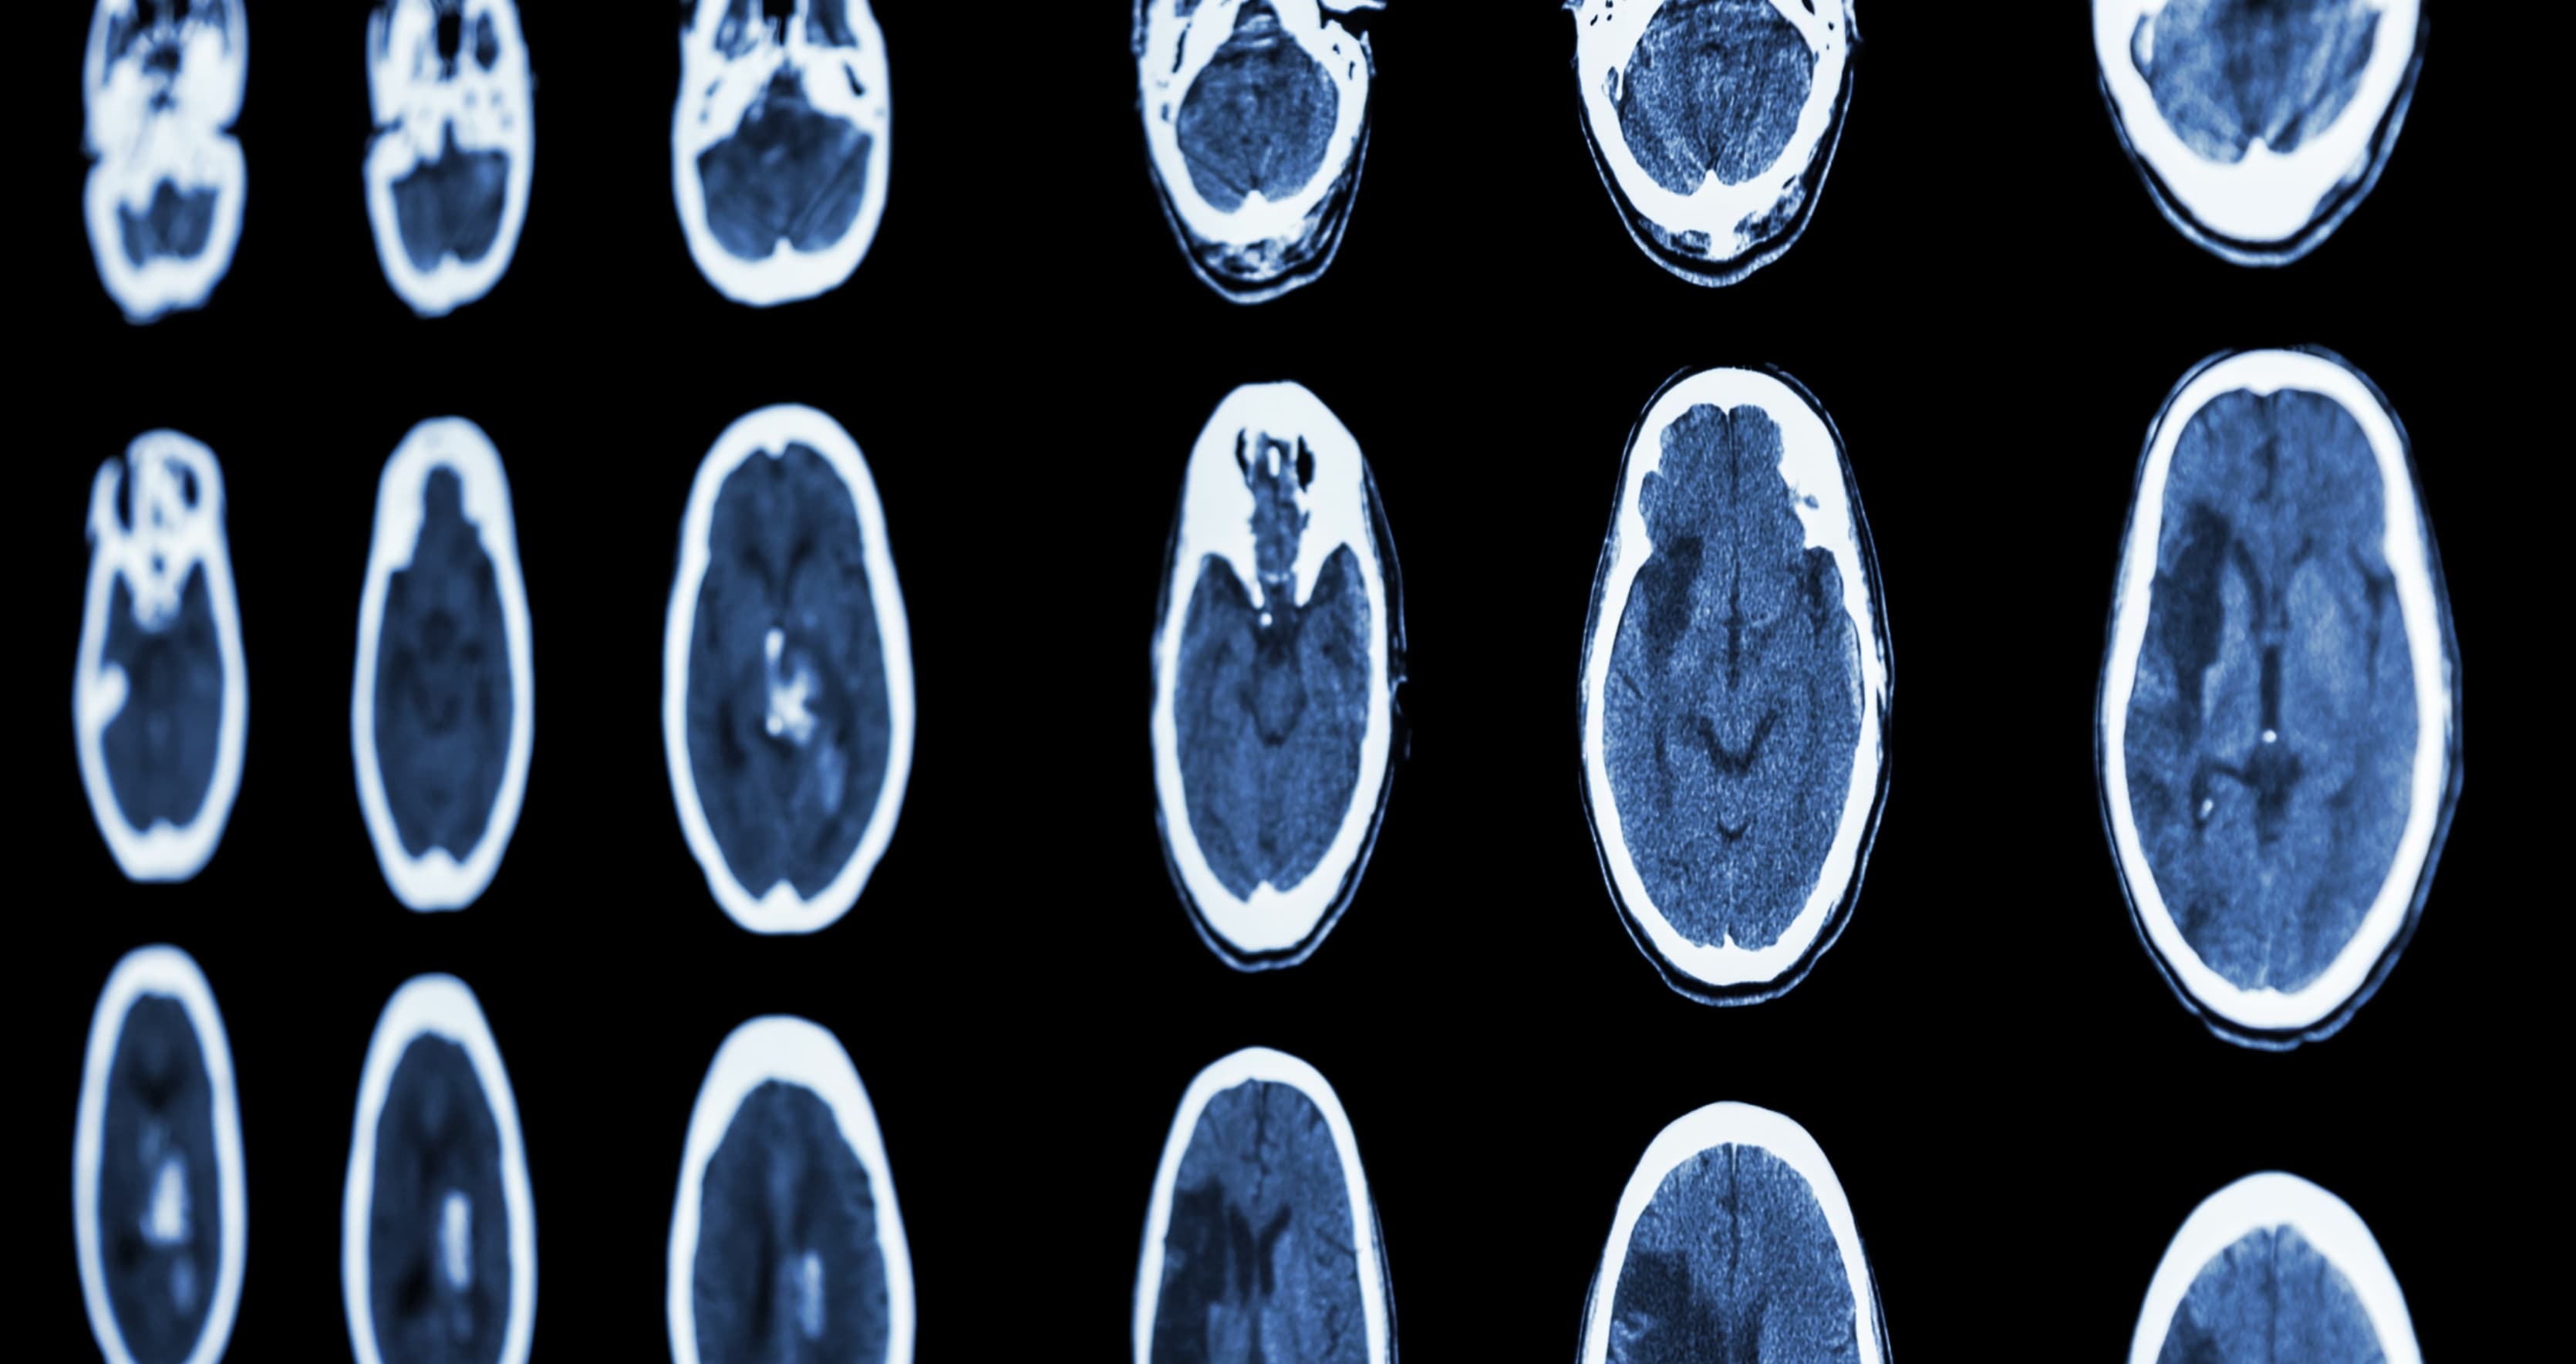

Grâce à l’IRM couplée à l’intelligence artificielle, nous saurons demain repérer la typologie du caillot bouchant l’artère pour donner, en urgence, le traitement le plus efficace.